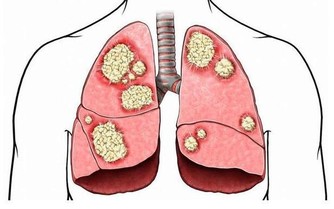

3. 晚餐與腸癌

晚餐若吃過飽,蛋白質食物無法完全消化。

在腸道細菌的作用下,產生有毒物質,

加上活動量小使得腸壁蠕動緩慢,延長有毒物質滯留時間,增加腸癌風險。